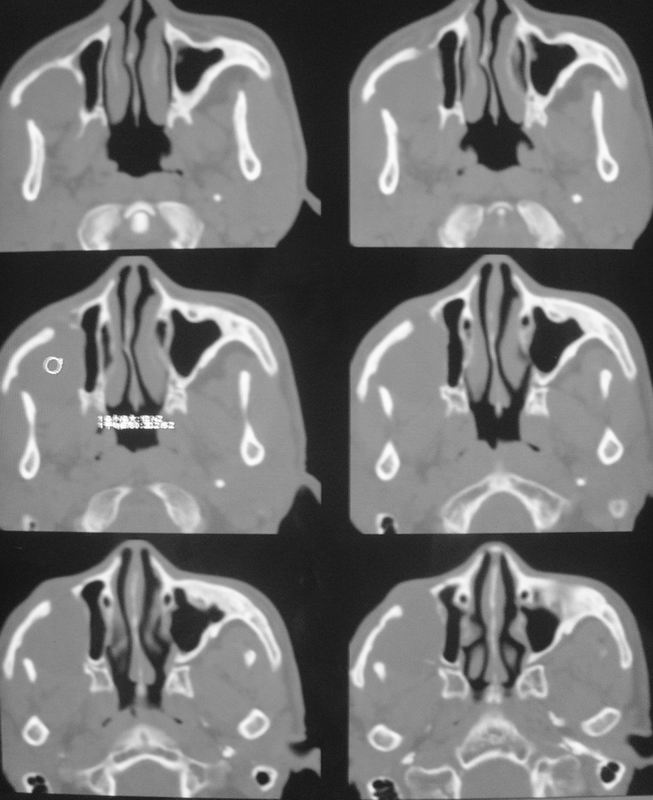

以下是引用zsl6918在2008-5-6 14:41:00的发言:[br]右侧颞下窝内囊性占位(增强未见强化),同侧上颌窦受压变形移位,提示慢性过程。右侧上颌骨局限性吸收破坏,提示良性病变。

以下是引用xuhuihong在2008-5-6 14:57:00的发言:[br]右侧颞下窝内囊性占位(增强未见强化),同侧上颌窦受压变形移位骨质吸收变薄,提示慢性过程。右侧上颌骨局限性吸收破坏,提示良性病变。考虑神经源性肿瘤可能,期待结果。